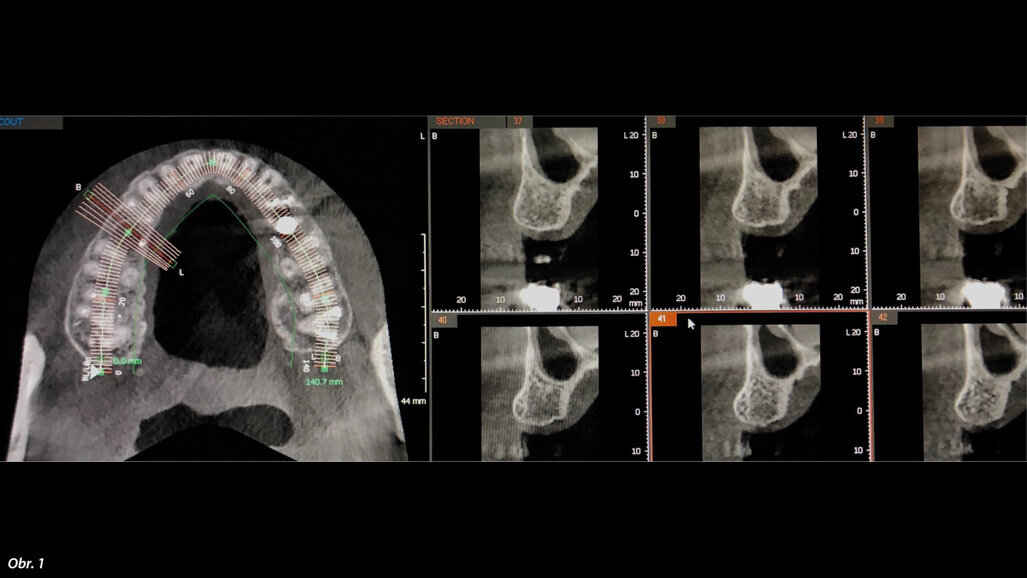

Dr Lakhani enlightened the audience with his detailed lecture regarding the various applications of CBCT and its widespread use in Dentistry and Maxillofacial surgery.

The Defence 3D-OPG-CEPH team gave the participants a visual demonstration of software usage tools at the JMDC computer lab, followed by a hands-on session. The college also looks forward to launch the software in different dental departments and to make it accessible for all.